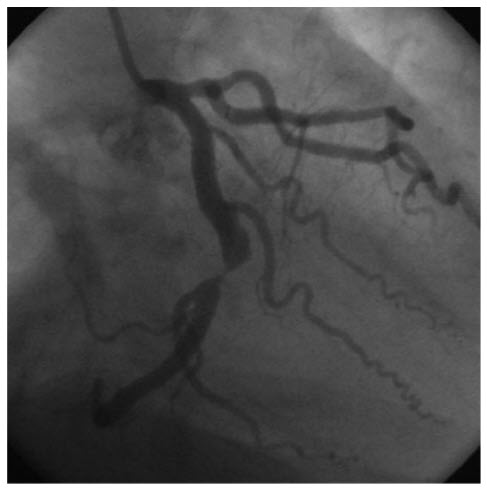

A 54-year-old man known for smoking and hypertension is admitted to the emergency department with an NSTEMI. Echocardiography reveals abnormalities in the acute lateral wall motion. The angiogram (Fig. below)

shows

Severe LCX stenosis. The coronary angiography of the left circulation shows severe mid-left circumflex coronary artery stenosis.